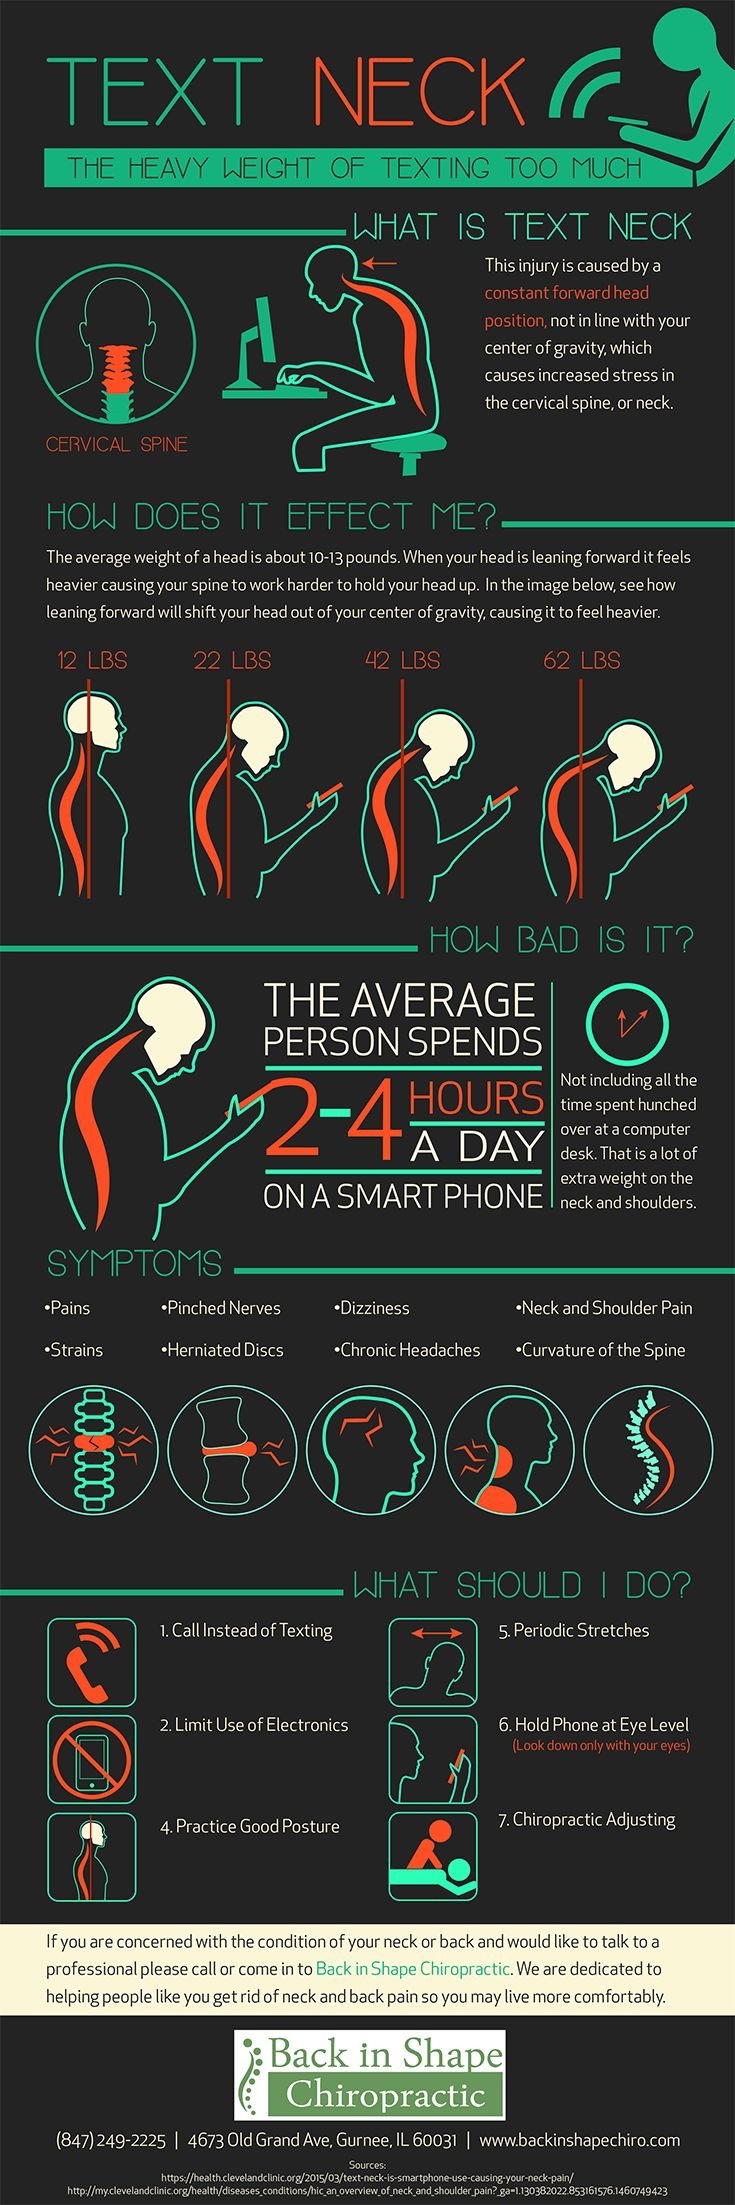

スマホ姿勢になってませんか?

スマホ姿勢になってませんか?

スマホ習慣の見直し(Posture Month)

スマホ習慣の見直し(Posture Month)

"Text Neck" : テキストネック

"Text Neck" : テキストネック